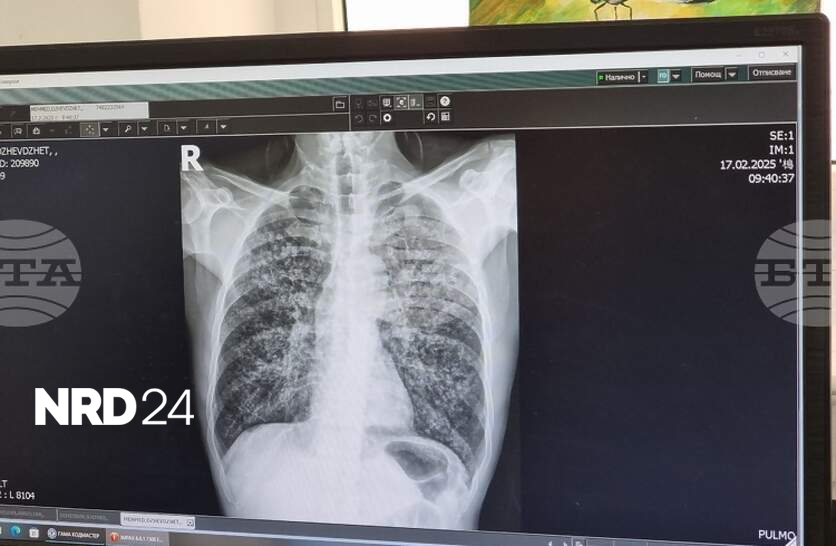

Общо 26 случая на туберкулоза са регистрирани до края на ноември в ПазарджишкоОбщо 26 са регистрираните случаи на туберкулоза до края на ноември в Пазарджишка област, съобщиха от Регионалната здравна инспекция по повод кампанията за превенция на заболяването, която започва на 8 декември.До края на работната седмица в "Специализирана болница за активно лечение на пневмо- фтизиатрични заболявания - д-р Никола Пенчев- Пазарджик " ще има безплатен скрининг за туберкулоза чрез анкета и консултация, а на хора, които са в риск, ще се извършват допълнителни прегледи и изследвания.

Общо 26 са регистрираните случаи на туберкулоза до края на ноември в Пазарджишка област, съобщиха от Регионалната здравна инспекция по повод кампанията за превенция на заболяването, която започва на 8 декември. До края на работната седмица в "Специализирана болница за активно лечение на пневмо- фтизиатрични заболявания - д-р Никола Пенчев- Пазарджик " ще има безплатен скрининг за туберкулоза чрез анкета и консултация, а на хора, които са в риск, ще се извършват допълнителни прегледи и изследвания. Кампанията "Седмица на отворените врати" се осъществява в изпълнение на Националната програма за превенция и контрол на туберкулозата в България за периода 2021 – 2025 г. През тази година кампания за превенция на туберкулозата беше проведена и през юни.